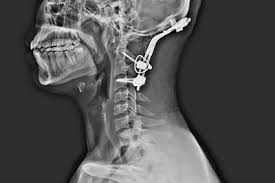

Cervical Disc Surgery in Nagpur at Kakani's Brain Spine and Dental Super Speciality Clinic

Doctors begin with a detailed neurological evaluation, assessing reflexes, motor strength, and sensory function. Meanwhile, imaging studies such as MRI or CT scans visualize disc condition, nerve compression, and spinal alignment. Additionally, laboratory tests may rule out infections or inflammatory conditions. Consequently, precise diagnosis ensures proper intervention and prevents further neurological deterioration.